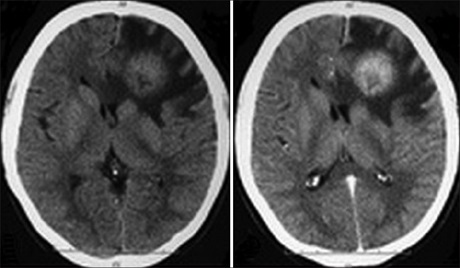

Cerebral Aspergilloma Mimicking Tumoral Mass: A Diagnostic Dilemma

Intracranial aspergillosis infection is very rare in immunocompetent patients. Among its varied presentations a solitary intracranial mass is very uncommon. It is usually misdiagnosed as tumor or abscess. A high index of clinical suspicion coupled with an early diagnosis can potentially be life saving. Because of its rarity in the immunocompetent patient and difficultly in preoperative diagnosis we illustrate this case.